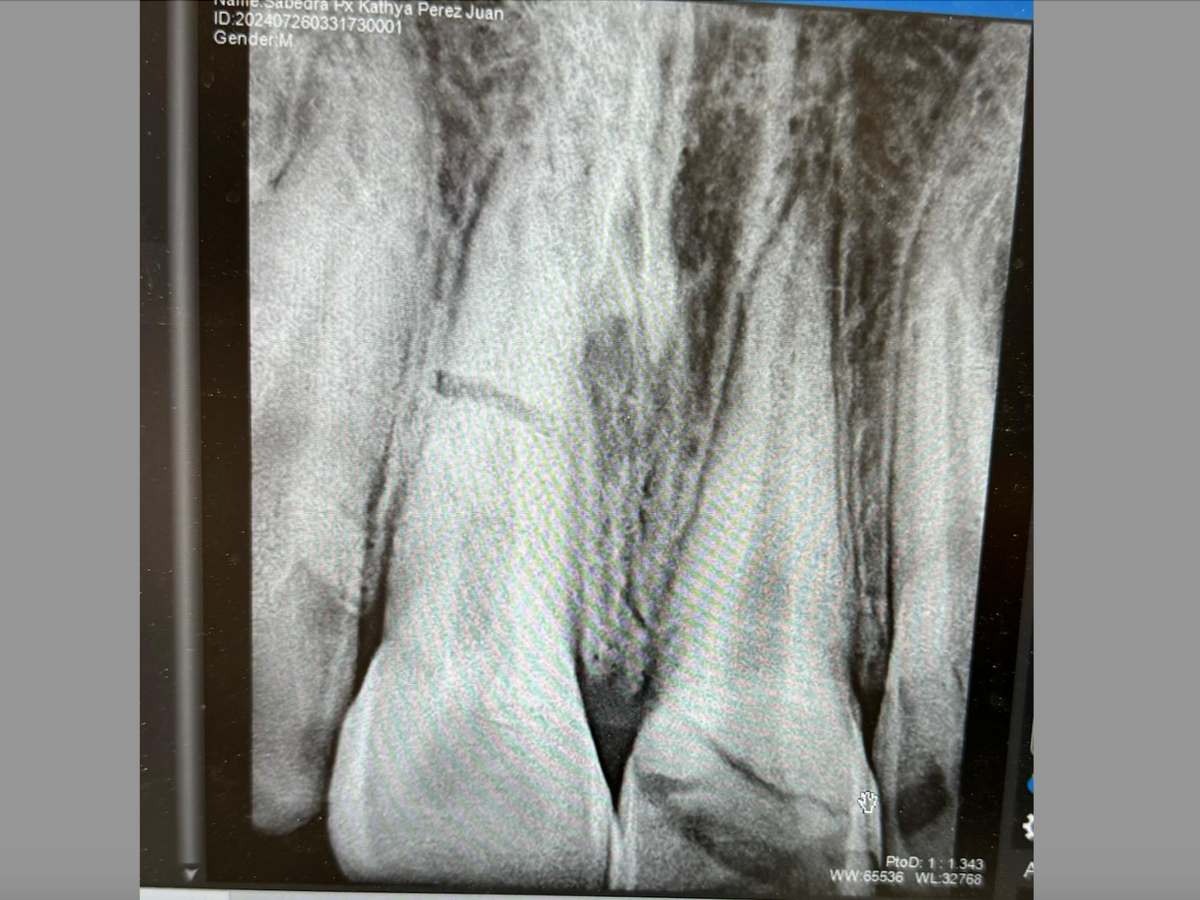

Él se golpeó los dos dientes frontales en un accidente, uno de ellos no se pudo rescatar, siendo necesario realizar endodocia y colocar una corona que usará mientras cumple la mayoría de edad, posteriormente se evaluara si necesita cambio, el otro diente se le fracturó de la raíz en este caso el diente estará en observación durante aproximadamente 6 meses para tratar salvarlo. Buscamos lograr apoyarlo para que pueda solventar los gastos de este tratamiento el cuál no es un proceso fácil, esperamos poder contar con su apoyo